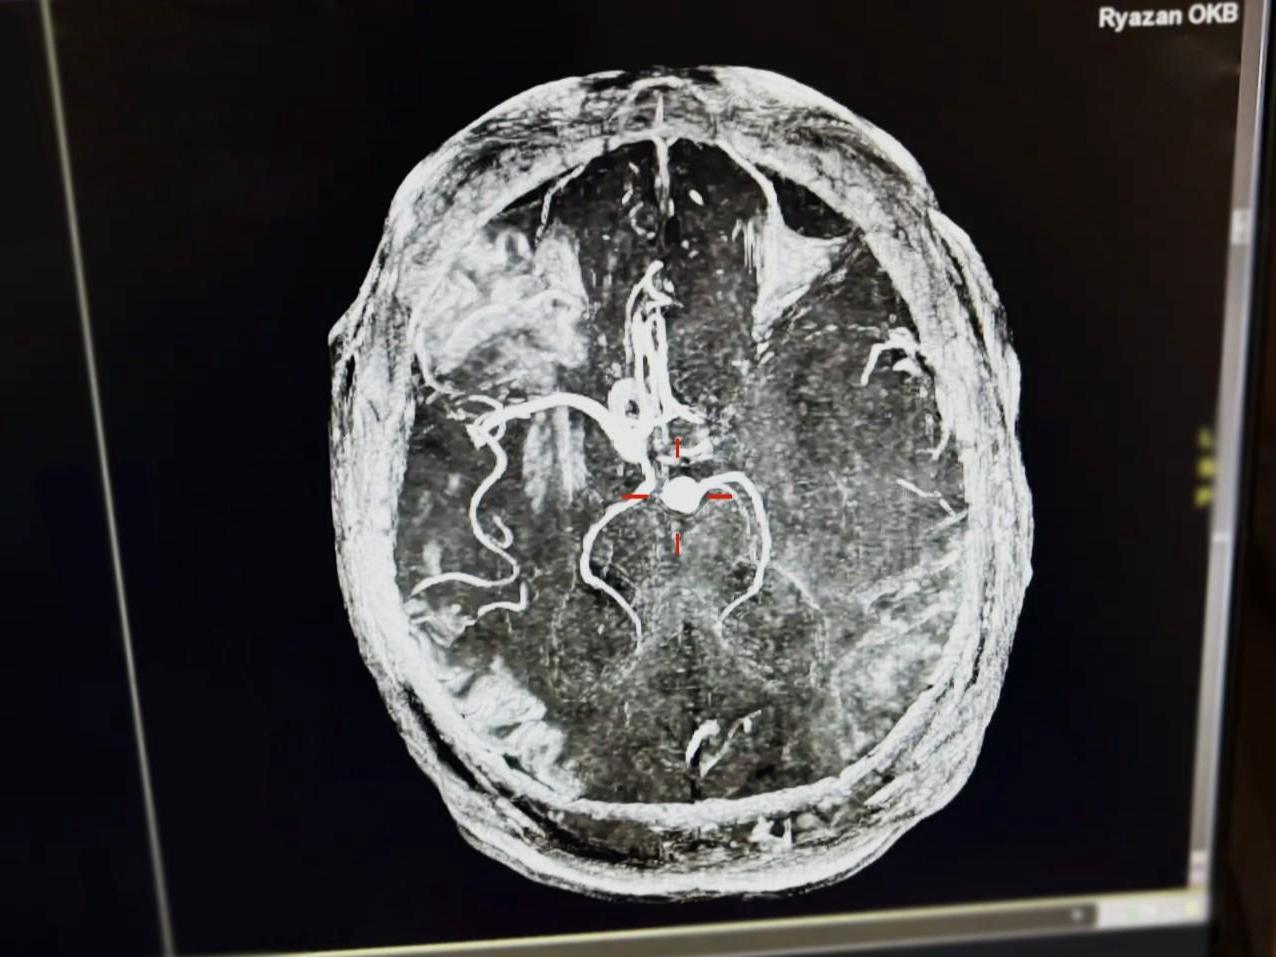

An MRI scan shows the brain of the patient who suffered a stroke after consuming energy drinks.

The patient«s wife called an ambulance and reported that her husband had numbness in the left side of his body and impaired coordination. The man was taken to the Regional Clinical Hospital (OKB) with suspected stroke. At the hospital, his blood pressure was measured at 265/155, confirming the stroke.

Doctors at the Regional Clinical Hospital (OKB) dissolved the blood clot and restored blood flow in the blocked vessel. Over the five days the patient was under observation, his blood pressure stabilized and his condition improved. He has now been discharged for further monitoring at his place of residence, as reported on the social media of the regional clinical hospital.